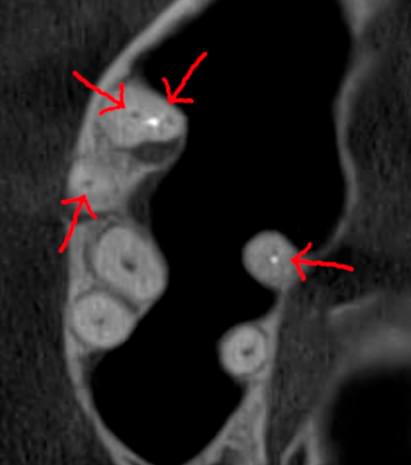

Коли коріння «ховає сюрпризи» - Корені зубів часто мають складну кривизну, гачкоподібні закручення або розгалуження, які на звичайному 2D-знімку накладаються один на одного, створюючи ілюзію прямого каналу. На плоскій картинці неможливо побачити реальний об'єм та напрямок вигину, що критично важливо при видаленні «зубів мудрості» або ендодонтичному лікуванні. КТ MyRay дає змогу лікарю заздалегідь побачити 3D-геометрію кожного кореня, оцінити його близькість до нижньощелепного нерва чи гайморової пазухи та підібрати правильну тактику роботи. Це мінімізує ризики поломки інструменту в каналі або травмування сусідніх структур, перетворюючи складну хірургію на прогнозовану процедуру.

Часто причиною зубного болю є гайморит, і навпаки — причиною запалення пазух є хворий зуб. На звичайному знімку пазуха виглядає як темна пляма. На КТ ми бачимо стан слизової, наявність кіст або сторонніх тіл (наприклад, залишків пломбувального матеріалу), що критично важливо для правильного діагнозу.